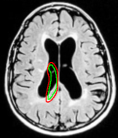

Refer to captionRefer to caption(a)(b)Refer to captionRefer to caption𝑎𝑏\begin{array}[]{cc}\includegraphics[width=108.405pt]{hindi_init.pdf}&\includegraphics[width=108.405pt]{hindi-result-1.pdf}\\ (a)&(b)\end{array}

Figure 14: Segmentation of left lateral ventricle: (a) Initialization with a template (b) converged contour. Image source: Intermountain Medical Imaging, Idaho.

In Figure 13, we show the results for segmentation of endocardium in B-mode ultrasound images, an imaging modality where shape prior information is popularly[40, 41] used to counter the problem of broken/diffuse boundaries between the region of interest and its background. In Figure 14, we show an example where the template based formulation is able to overcome partial loss of signal due to occlusion and still segment the object reliably. We observe that, by incorporating prior knowledge of the shape, we can segment images with partial loss of structure and broken boundaries.

When the object is sparsely surrounded by competing regions, we observed that the segmented output is not critically dependent on the width of the annular region. The energy functional is well behaved without local minima affecting its performance. Figure 18 illustrates a case where the left ventricle in a MR scan of the brain is segmented with templates differing in their annular widths. An inner template is chosen and the width of the annular region is changed to generate these four templates. The right ventricle has same intensity profile as that of the left ventricle. This causes the right ventricle to become a potentially competing region, but the results indicate identical segmentation outputs despite the outer contour overlapping with the right ventricle to varying degrees in Figures 18(a), (b), (c), and (d) respectively. The experiment is repeated with multiple initializations and the consistency in final output is observed.

Refer to captionRefer to captionRefer to captionRefer to caption(a)(b)(c)(d)Refer to captionRefer to captionRefer to captionRefer to caption𝑎𝑏𝑐𝑑\begin{array}[]{cccc}\includegraphics[width=108.405pt]{15.pdf}&\includegraphics[width=108.405pt]{25.pdf}&\includegraphics[width=108.405pt]{35.pdf}&\includegraphics[width=108.405pt]{45.pdf}\\ (a)&(b)&(c)&(d)\end{array}

Figure 18: (a), (b), (c), and (d) are the converged results using various templates that share the same contour for the inner template and differ only in their outer template. The annular widths of the template in (a), (b), (c), and (d) are 15, 25, 35 and 45 pixels, respectively. The MR scan is taken from [44].